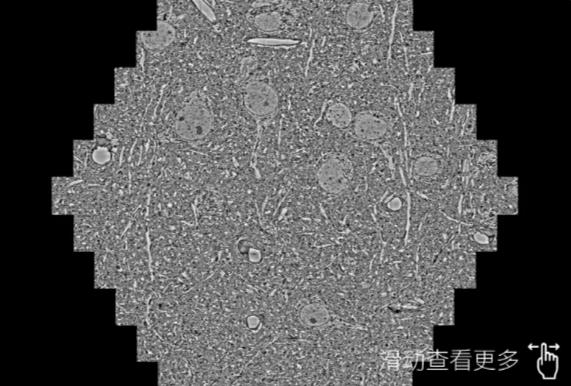

鼠脑切片。左图使用钦州蔡司钦州扫描电镜MultiSEM706对165μmx143pm面积区域成像,耗时仅需1.5秒。右图为鼠脑切片中30μm区域放大效果。样品由芝加哥大学B.Kasthuri提供。

使用蔡司高速钦州扫描电镜MultiSEM对1mm²人脑皮层组织进行高分辨成像,并对其中的各种细胞结构进行三维重构分析。左图展示了2x3mm²组织平面中锥体神经元的三维重构效果。右图显示了局部体积神经元三维重构。图像由哈佛大学chtman实验室提供,渲染图由D. Berger 制作。